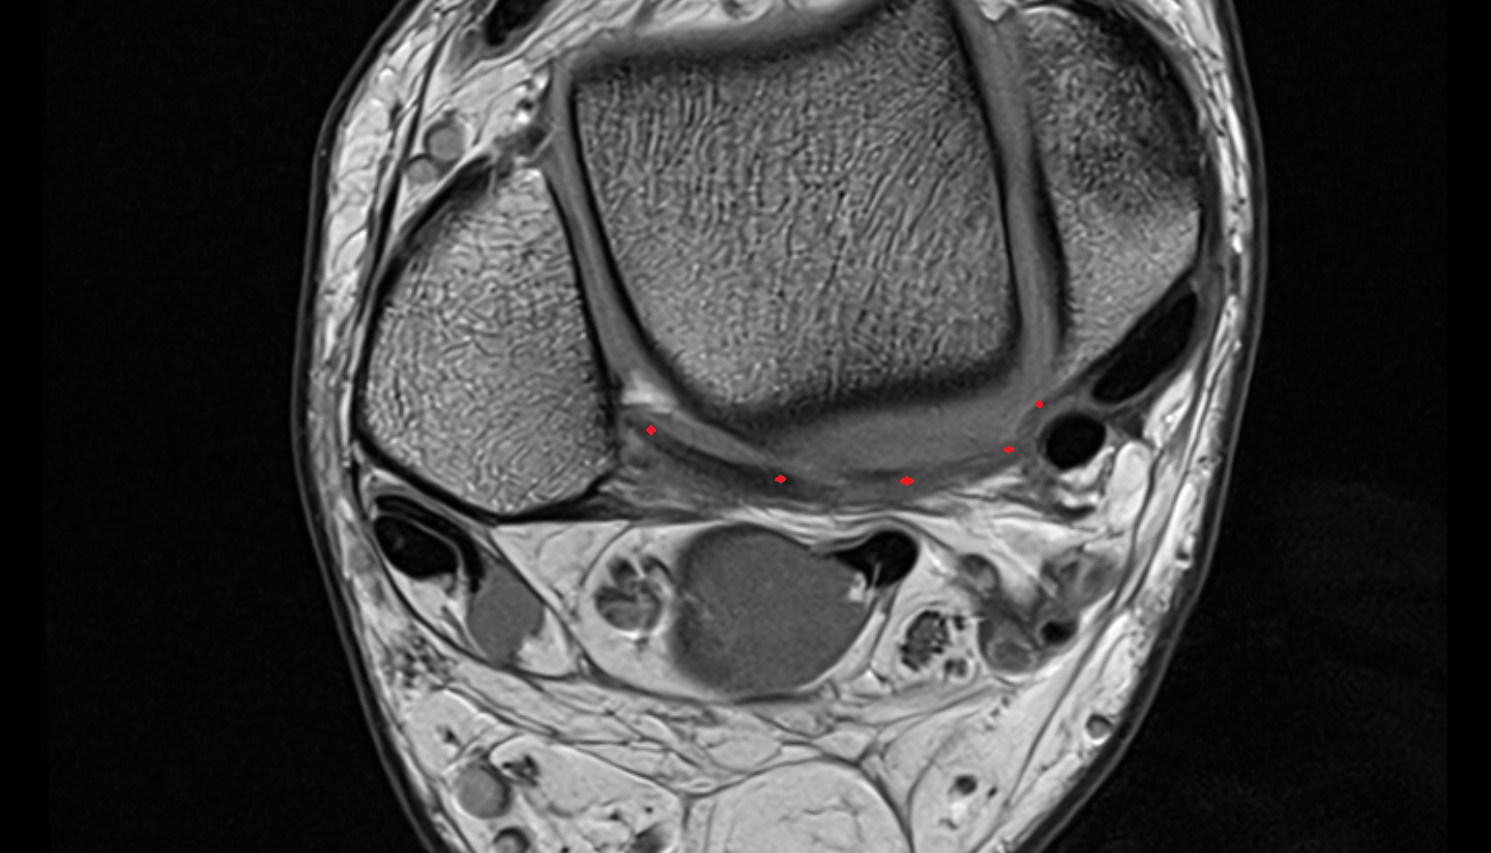

- Medial meniscus

- Lateral meniscus